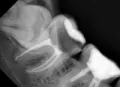

Восьмой зуб вверху вырос в щеку и на нем сейчас есть дырка, наверное, из-за кариеса. Можно вылечить или удалять?

Восьмые зубы необходимо удалить все, можно оставить только 48, он стоит в зубном ряду и не создаёт скученность, и не страдает соседняя семерка. Во всех трёх остальных случаях Ваши зубы мудрости необходимо удалить как можно раньше.